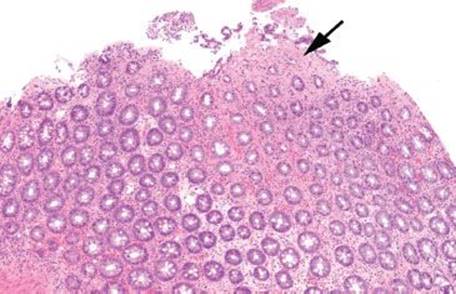

Figure 4.55 Ischemic colitis pattern. This low magnification image emphasizes the microcrypt pattern. Small, withered crypts are present (arrow) along with lamina propria hyalinization. Note the homogenous pink appearance of the lamina propria in the area of the arrow. By comparison, the lamina propria at the base of the field is still preserved.

Mucosal ischemia causes a highly characteristic pattern of injury, including features of surface injury, loss of mucin, lamina propria hemorrhage and hyalinization, withered crypts, atrophic microcrypts, and lamina propria collapse (Fig. 4.50). The architectural pattern of withered crypts and microcrypts is distinctive at low magnification, and one might even refer to this pattern of injury as the “microcrypt pattern” (Fig. 4.51). Although ischemic injury is top among the differential diagnoses, other considerations include vascular injury (such as that seen in radiation colitis, amyloidosis, or vasculitis), infection (particularly Escherichia coli 0157:H7 and Clostridium difficile), and medications (NSAIDs, Kayexalate, and sevelamer).

Decreased blood flow and lack of oxygen to the GI tract result in necrosis or tissue damage, causing ischemia. There are several weak points in the colonic blood supply, known as watershed areas, which result from incomplete anastomosis of the marginal arteries and lack of sufficient collateral circulation. These watershed areas are more vulnerable to ischemic injury than other parts of the colon and include the splenic flexure (or Griffith’s point), the rectosigmoid region at Sudeck’s point, and the ileocecal region. Among the older population, ischemic disease is typically attributable to atherosclerotic mesenteric vascular disease, but the causes of colonic ischemia are many (Table 4.2). The histologic findings are dependent on the timing of the ischemic event (Figs. 4.52–4.63). Early and minimal injury, for example, occurs first as degeneration and sloughing of superficial epithelial cells, edema, and vascular congestion. Later, the epithelial cells become markedly attenuated and the crypts appear compressed and atrophic (“microcrypts”) as the lamina propria swells and hemorrhages. Within 5 hours of total acute vascular occlusion, almost the entire intestinal wall appears necrotic. These changes are devoid of acute inflammation until reperfusion occurs. Paradoxically, reperfusion further injures the tissues by introducing oxygen free radical formation,16 the severity of which is dependent on the duration of the preceding hypoxia.